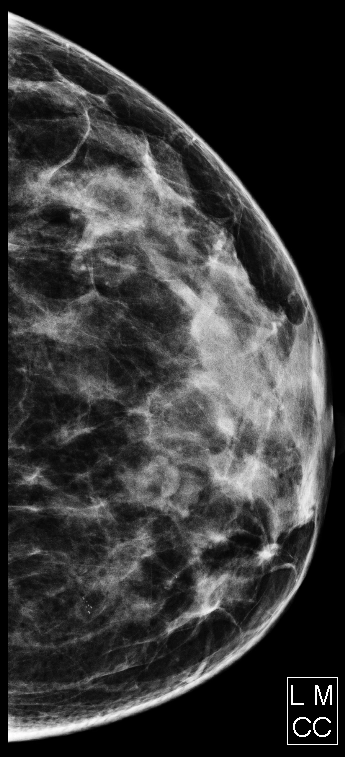

Vôi hóa tuyến vú (Breast calcifications)